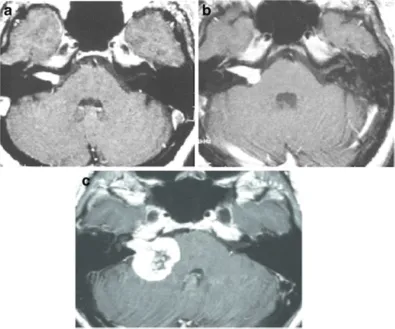

有个典型案例:一位58岁的女性,因为右耳听力下降、头晕查出听神经瘤,做了伽马刀治疗(边缘剂量12.3Gy)。放疗后两年,肿瘤轻度增大;到第三年,肿瘤明显变大并压迫脑干,患者完全失聪、严重共济失调,最后不得不接受手术。

图1 :A.轴位增强 MRI显示右侧内听道内肿瘤,均匀强化(伽玛刀治疗前);B.轴位增强 MRI 显示肿瘤向脑桥小脑角生长(伽玛刀治疗2年后);C.轴位增强 MRI 显示肿瘤进一步生长压迫脑干和小脑(伽玛刀治疗3年后),肿瘤中心未强化